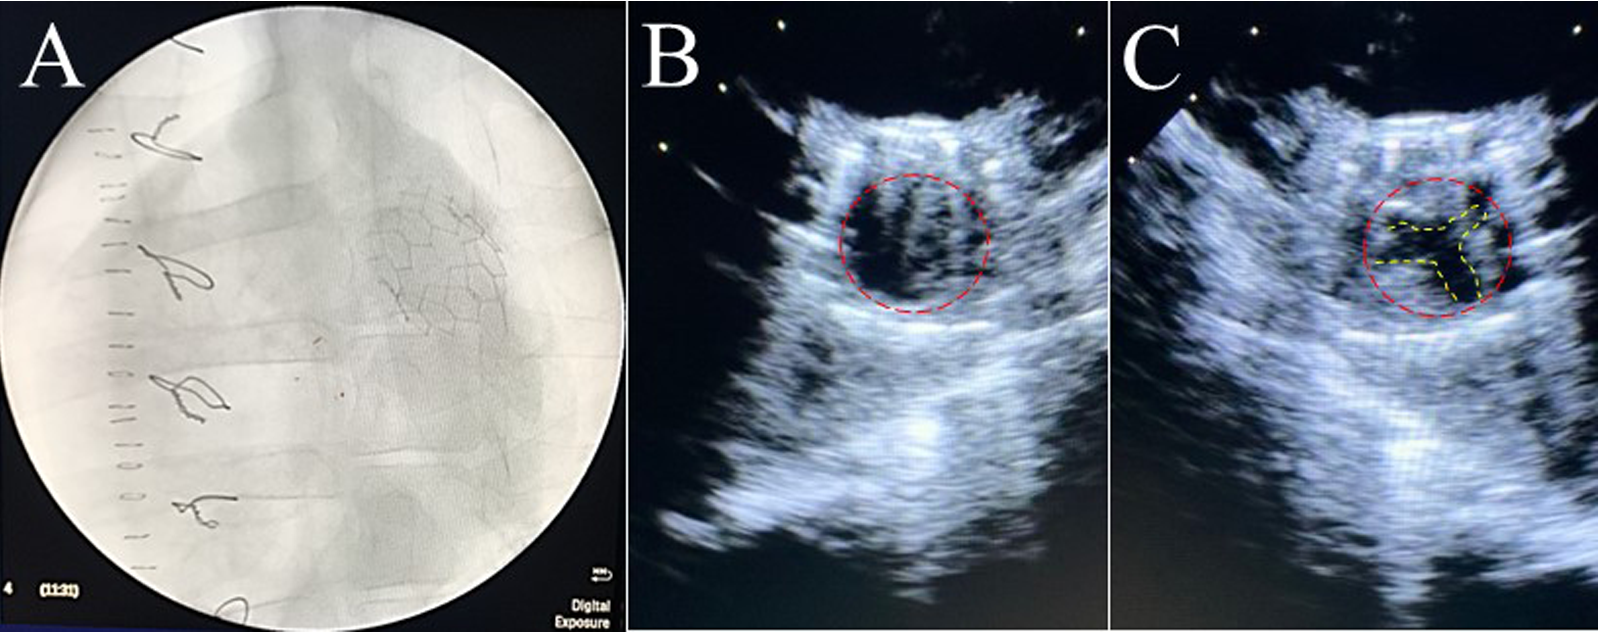

Six PVP bioprosthetic valves with cusps thicknesses of 0.17 ± 0.01 mm (n = 3) and 0.22 ± 0.015 mm (n = 3) were implanted in six pigs, respectively. While the PVP bioprosthetic valves were implanted at the junction of RVOT and pulmonary artery in pigs, no complications were observed in any animal during the postoperative period. In the terminal study, we did not observe any migration of the PVP bioprosthetic valves in the junction of RVOT and pulmonary artery until postoperative four months (Figure 2A). No right ventricular dilation was observed in fluoroscopy. The valve cusps opening and coaptation were observed by ICE (Figures 2B,C). In the post-mortem examination, we did not observe any thrombotic deposit, inflammation, or fibrosis in the heart and pulmonary artery (Figure 3A). Further dissection to expose the PVP bioprosthetic valves showed no thrombotic deposit, inflammation, or fibrosis on the valve cusps and skirt (Figure 3B). When the PVP bioprosthetic valves were isolated, we did not observe any calcific deposit on the valve cusps, valve skirt, or aortic wall (Figure 3C).

Figure 2

Fluoroscopic and ultrasound (ICE) images of a bioprosthetic valve in the pulmonary artery outflow tract of a pig. (A) Fluoroscopic image visualized the stent of a bioprosthetic valve in the pulmonary artery outflow tract of a pig. (B) Ultrasound image (transverse plane) showed the opening of a bioprosthetic valve in the pulmonary artery outflow tract of a pig. (C) Ultrasound image (transverse plane) showed the coaptation of a bioprosthetic valve in the pulmonary artery outflow tract of the pig.